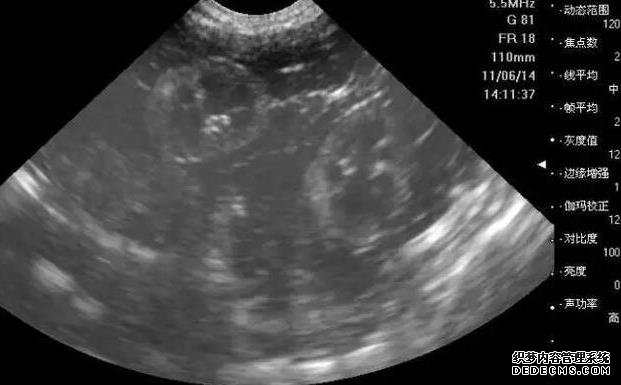

3、腹部彩超檢查:通過B超確定子宮內部環境是否正常,如大小形態如何、是否存在宮腔疾病,子宮內膜是否適合著床等。